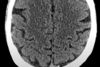

What level is this?

Identify structures.

Ventricles

Head of caudate, internal capsule, lentiform nucleus, thalamus, insular cortex, anterior temporal lobe.

Identify sylvian fissure (AKA). What artery runs along here?

What does the sylvian fissure separate?

Lateral sulcus

Middle cerebral artery

Frontal/Parietal lobe from temporal lobe